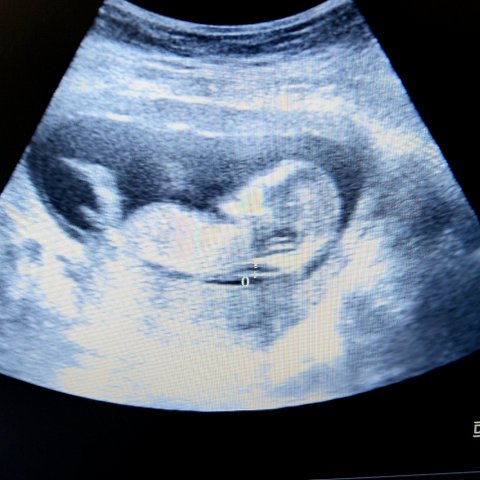

Như trên đã phân tích, từ tuần thứ 4 trái tim thai nhi đã có những nhịp đập nhẹ. Tuy nhiên để có thể xác định rõ ràng và chuẩn xác nhất thì các bác sĩ hoặc các cơ quan y tế thường khuyên các mẹ đi siêu âm vào tuần thứ 6 thậm trí là tuần 11, 14 để có thể lấy kết quả chính xác nhất.

Đối với thai nhi khỏe mạnh và phát triển bình thường thì nhịp tim sẽ dao động từ 120-160 lần/phút. Trong trường hợp trẻ di chuyển trong bụng mẹ thì khi siêu âm có thể lên đến 180 lần/phút. Theo sự phát triển của thai nhi, nhịp tim cũng sẽ dần đập nhanh hơn. Tuy nhiên trong trường hợp nhịp tim của trẻ lớn hớn 180 lần/phút thì đây có thể là dấu hiệu không tốt và cần được kiểm tra kĩ càng hơn.